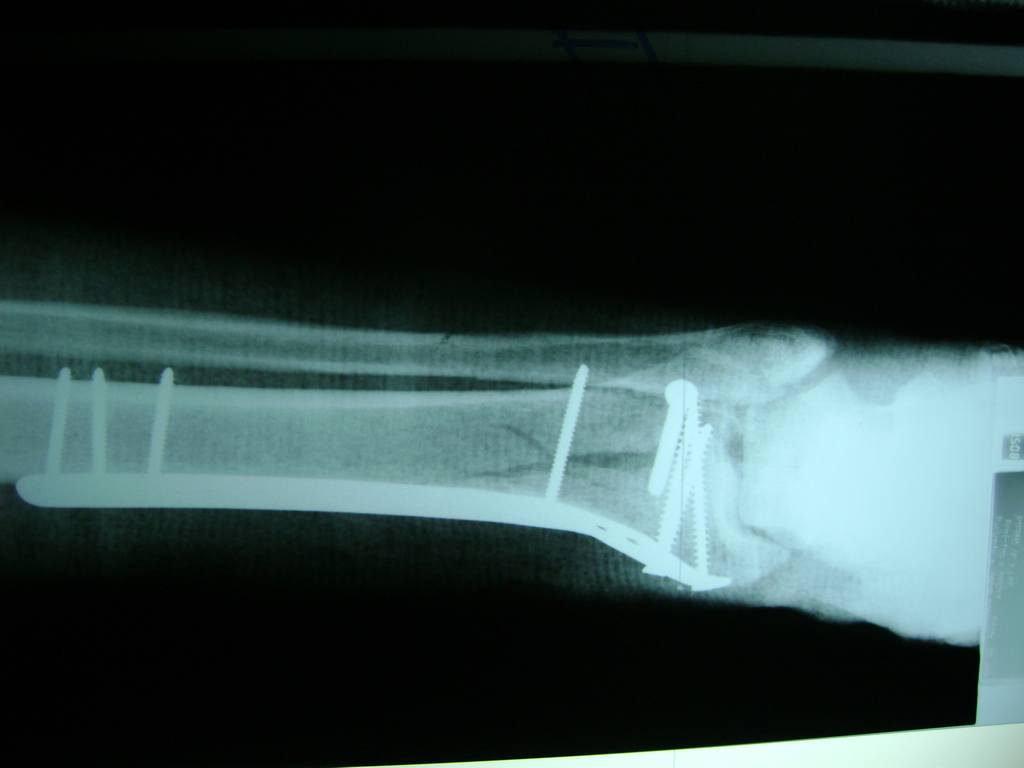

Cirugías

Aunque cada uno de estos huesos puede fracturarse por separado, normalmente la rotura es una lesión que se produce de forma conjunta

Debido a la fina cobertura de piel que recubre la tibia y el peroné, las fracturas generalmente son abiertas, es decir, el hueso roto rasga la piel, atravesándola. Las fracturas de tibia y peroné generalmente se producen por un fuerte impacto o torsión.